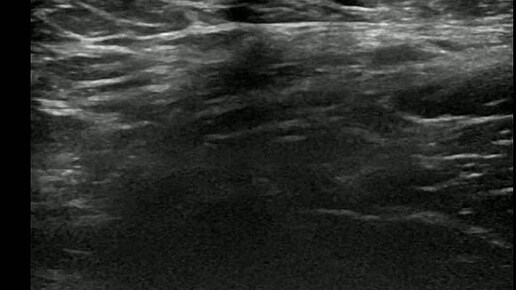

Видео к статье "Общие принципы ультразвуковой диагностики паховых грыж" https://dzen.ru/a/aC3gCR75zEo4_p-V